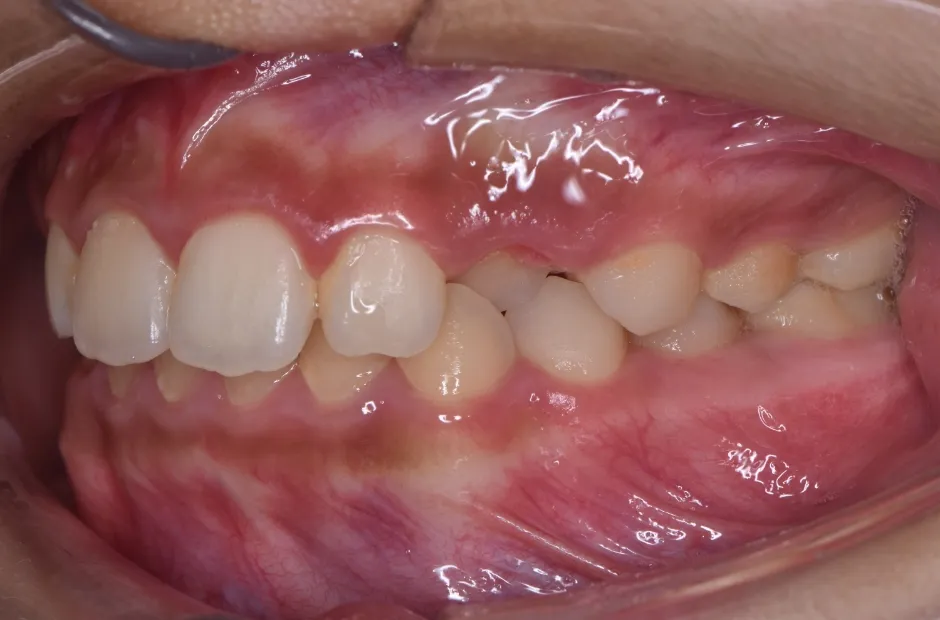

前歯部反対咬合

| 診断名・主訴 | 前歯部反対咬合 |

|---|---|

| 年齢・性別 | 14歳・男性 |

| 治療期間・回数 | 1年2か月 |

| 治療に用いた主な装置 | ブラケット矯正 |

| 抜歯部位 | なし |

| 治療費 | 60万円(税抜) |

| リスク・副作用 | 装置による違和感・疼痛・歯肉退縮・歯根吸収・虫歯のリスクなど |

治療前

治療後